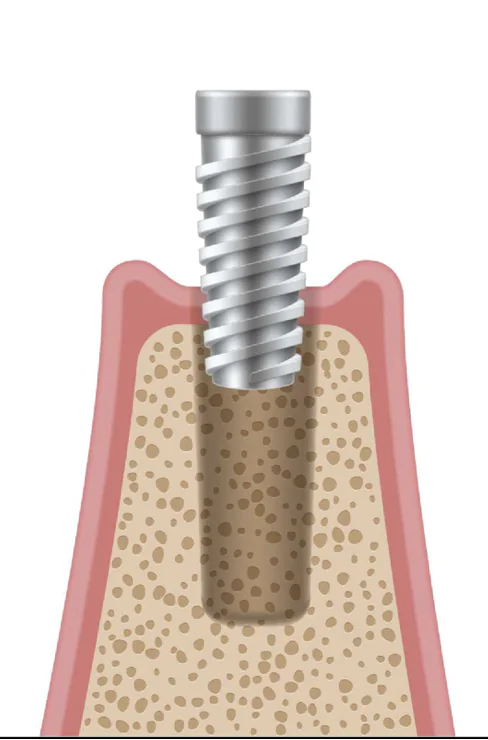

4インプラント埋入手術

当院では「即日インプラント」「1回法」「2回法」の3つの手法に対応しています。患者の骨の状態や埋入数などを考慮し、慎重な診断の上で最適な手法を提案しますインプラント体と顎の骨の結合に、通常約2~3ヶ月の治癒期間を設けます。この期間を経て、しっかりとした結合が形成され、安定した基盤が整います。

当院では「即日インプラント」「1回法」「2回法」の3つの手法に対応しています。患者の骨の状態や埋入数などを考慮し、慎重な診断の上で最適な手法を提案しますインプラント体と顎の骨の結合に、通常約2~3ヶ月の治癒期間を設けます。この期間を経て、しっかりとした結合が形成され、安定した基盤が整います。